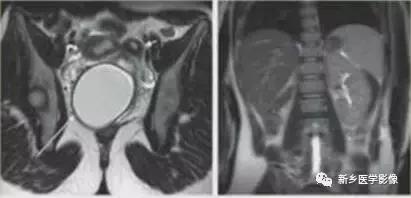

上图:单角子宫(II-B残角,有内膜腔,不相通):右侧残角宫腔内积血,为短T1长T2异常信号。左侧单角子宫,见带状结构,呈香蕉样。

上图:II-D无残角:右侧单角子宫,左侧无残角